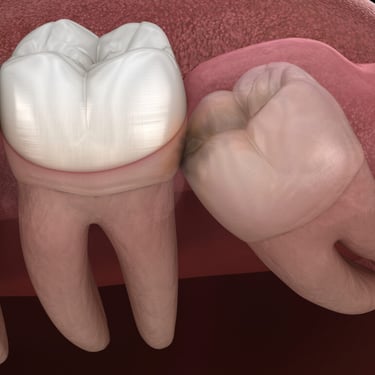

Dientes impactados

Los dientes impactados son dientes que no pueden erupcionar correctamente debido a la falta de espacio o a una obstrucción.

Los pacientes pueden notar que un diente no ha salido, aunque debería haberlo hecho. Esta condición es común con las muelas del juicio y los caninos superiores.

El tratamiento puede incluir la extracción del diente impactado o la creación de espacio para permitir su erupción.